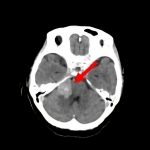

断層撮影